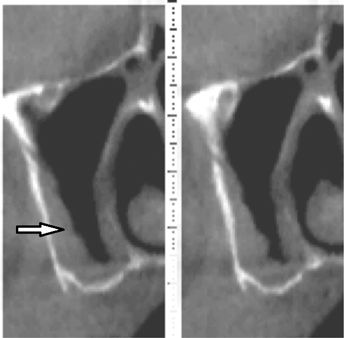

Fig 4. Mental foramen: cross-sectional view. Three branches of the mental nerve emerge from the foramen. The buccal radiolucency (mental foramen) is very distinct and provides a useful landmark when assessing cross-sections of a CBCT scan (arrow).

Figure 4